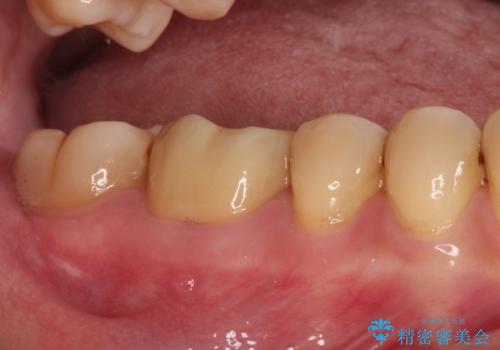

フルジルコニアクラウンは、やや光沢のある材質ですが、奥歯に装着した場合にはさほど気にならず、自然な口元の印象となりました。